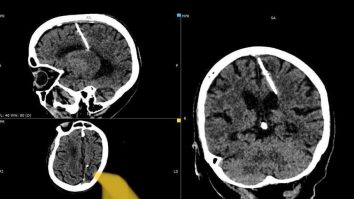

O femeie a trăit toată viața cu un ac de 3 cm în creier. Ce ipoteze au medicii despre cazul bătrânei

O pacientă suferise un AVC a fost rănită de o bucată de metal în computerul tomograf